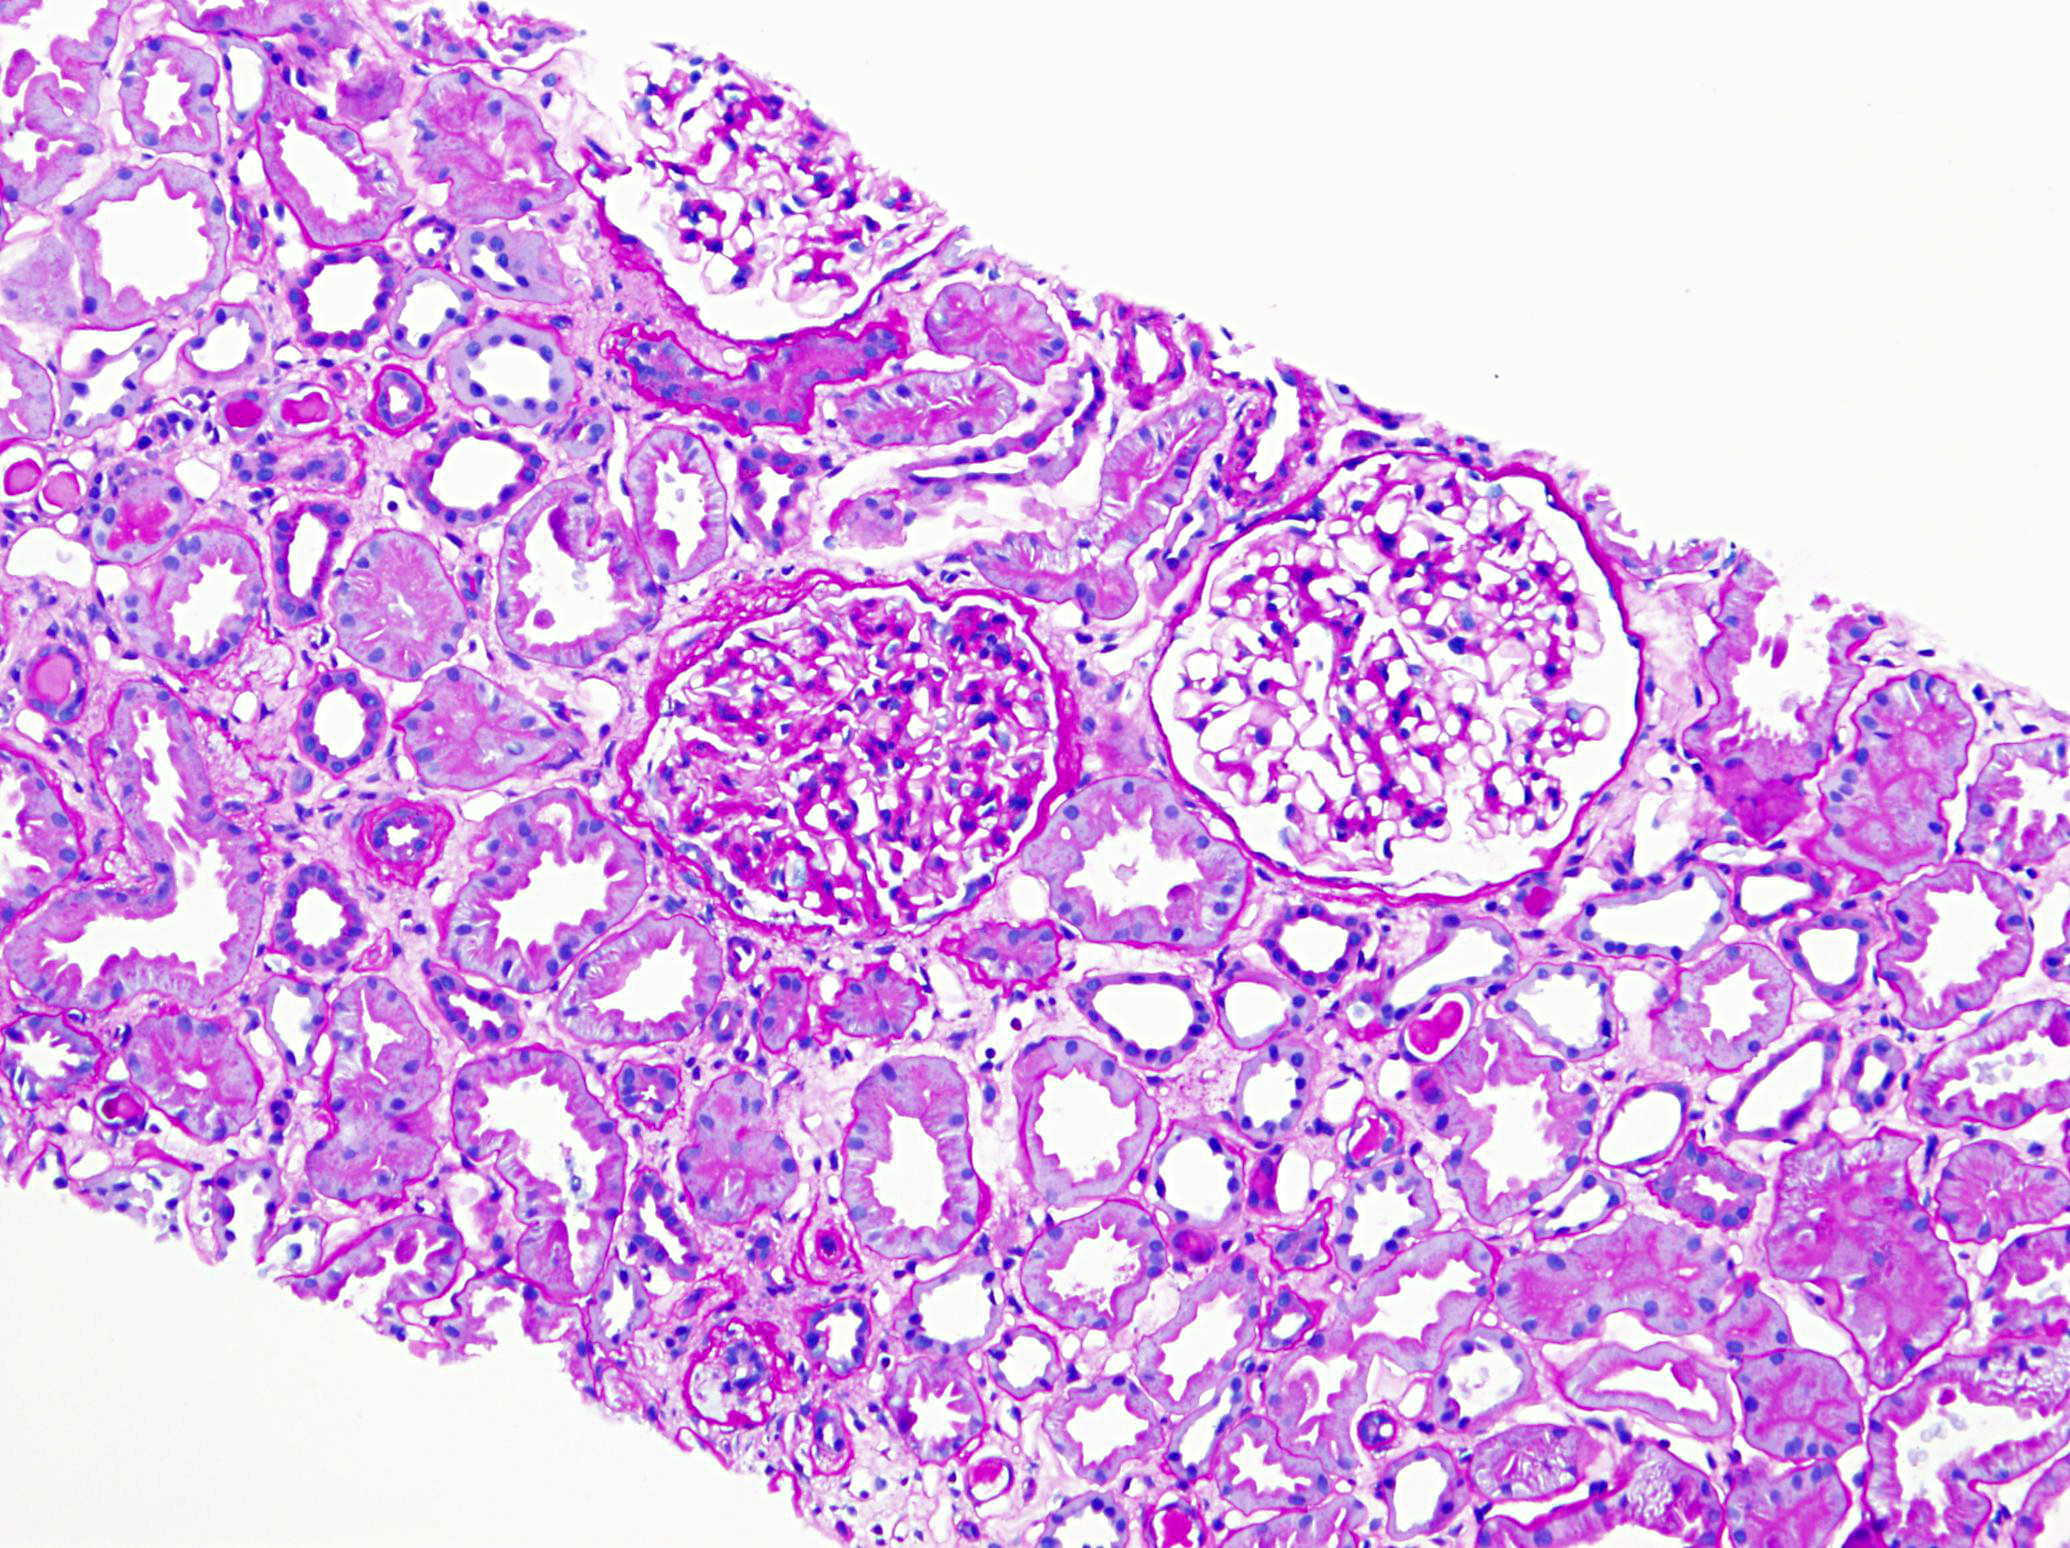

A 71-year-old man with long standing history of hypertension presented with...